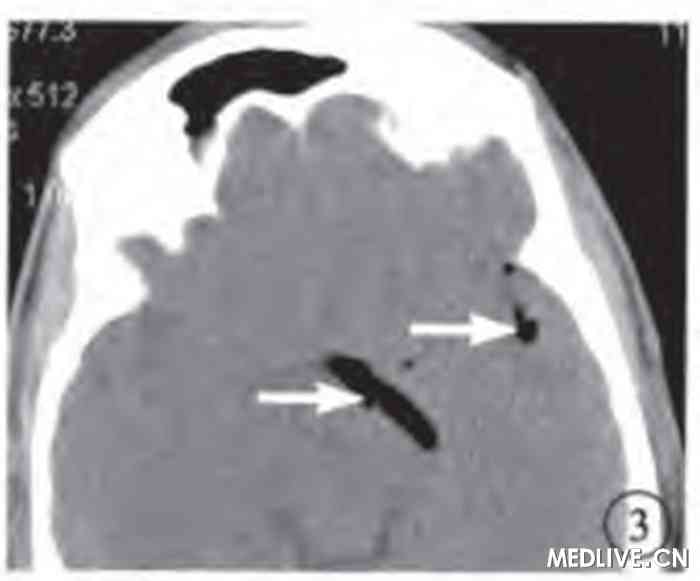

图3 玻璃体腔气体抽出手术前左眼CT横断面软组织窗像。蛛网膜下腔内散在积气(白箭)。

手术后第1天行CT检查显示,玻璃体腔、球后视神经鞘内积气消失,球壁增厚,脑内蛛网膜下腔仍存有少量积气(图4,5)。

图5 玻璃体腔气体抽出手术后CT横断面软组织窗像。蛛网膜下腔内仍有少量积气(白箭)。